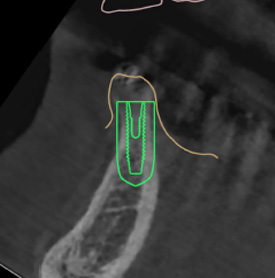

덴티스 - 심플가이드

오스템 - 원가이드

디오 - 디오나비